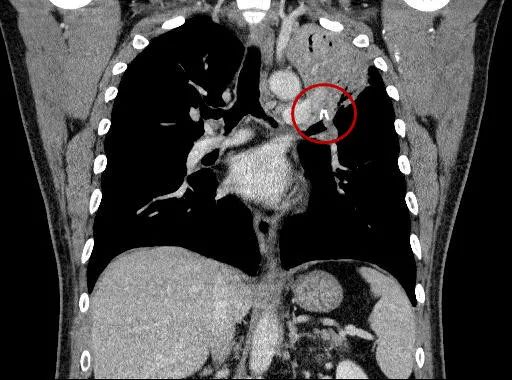

肺CT下的异物

从肺CT和支气管镜下可见,由于笔帽在支气管内时间长达35年之久,不断刺激支气管黏膜,引起局部增生,导致左侧上叶尖后段支气管已经被包绕笔帽的肉芽组织完全阻塞,钳后还伴有脓液溢出,取出难度极大,且容易出血或损伤气管。